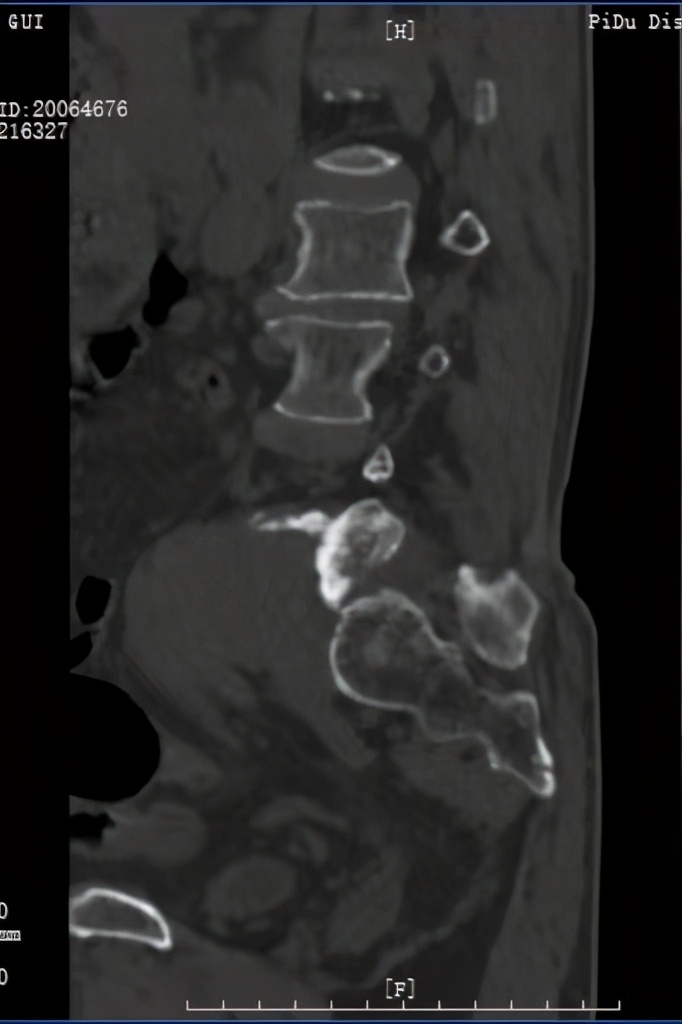

术前CT及MRI检查发现腰5/骶1椎管及左侧神经根管、椎旁软组织肿块

经过术前的检查和邓主任丰富的临床经验,使诊断渐趋明朗, 邹大爷的肿瘤需要进行手术切除,任其发展会产生严重的后果。